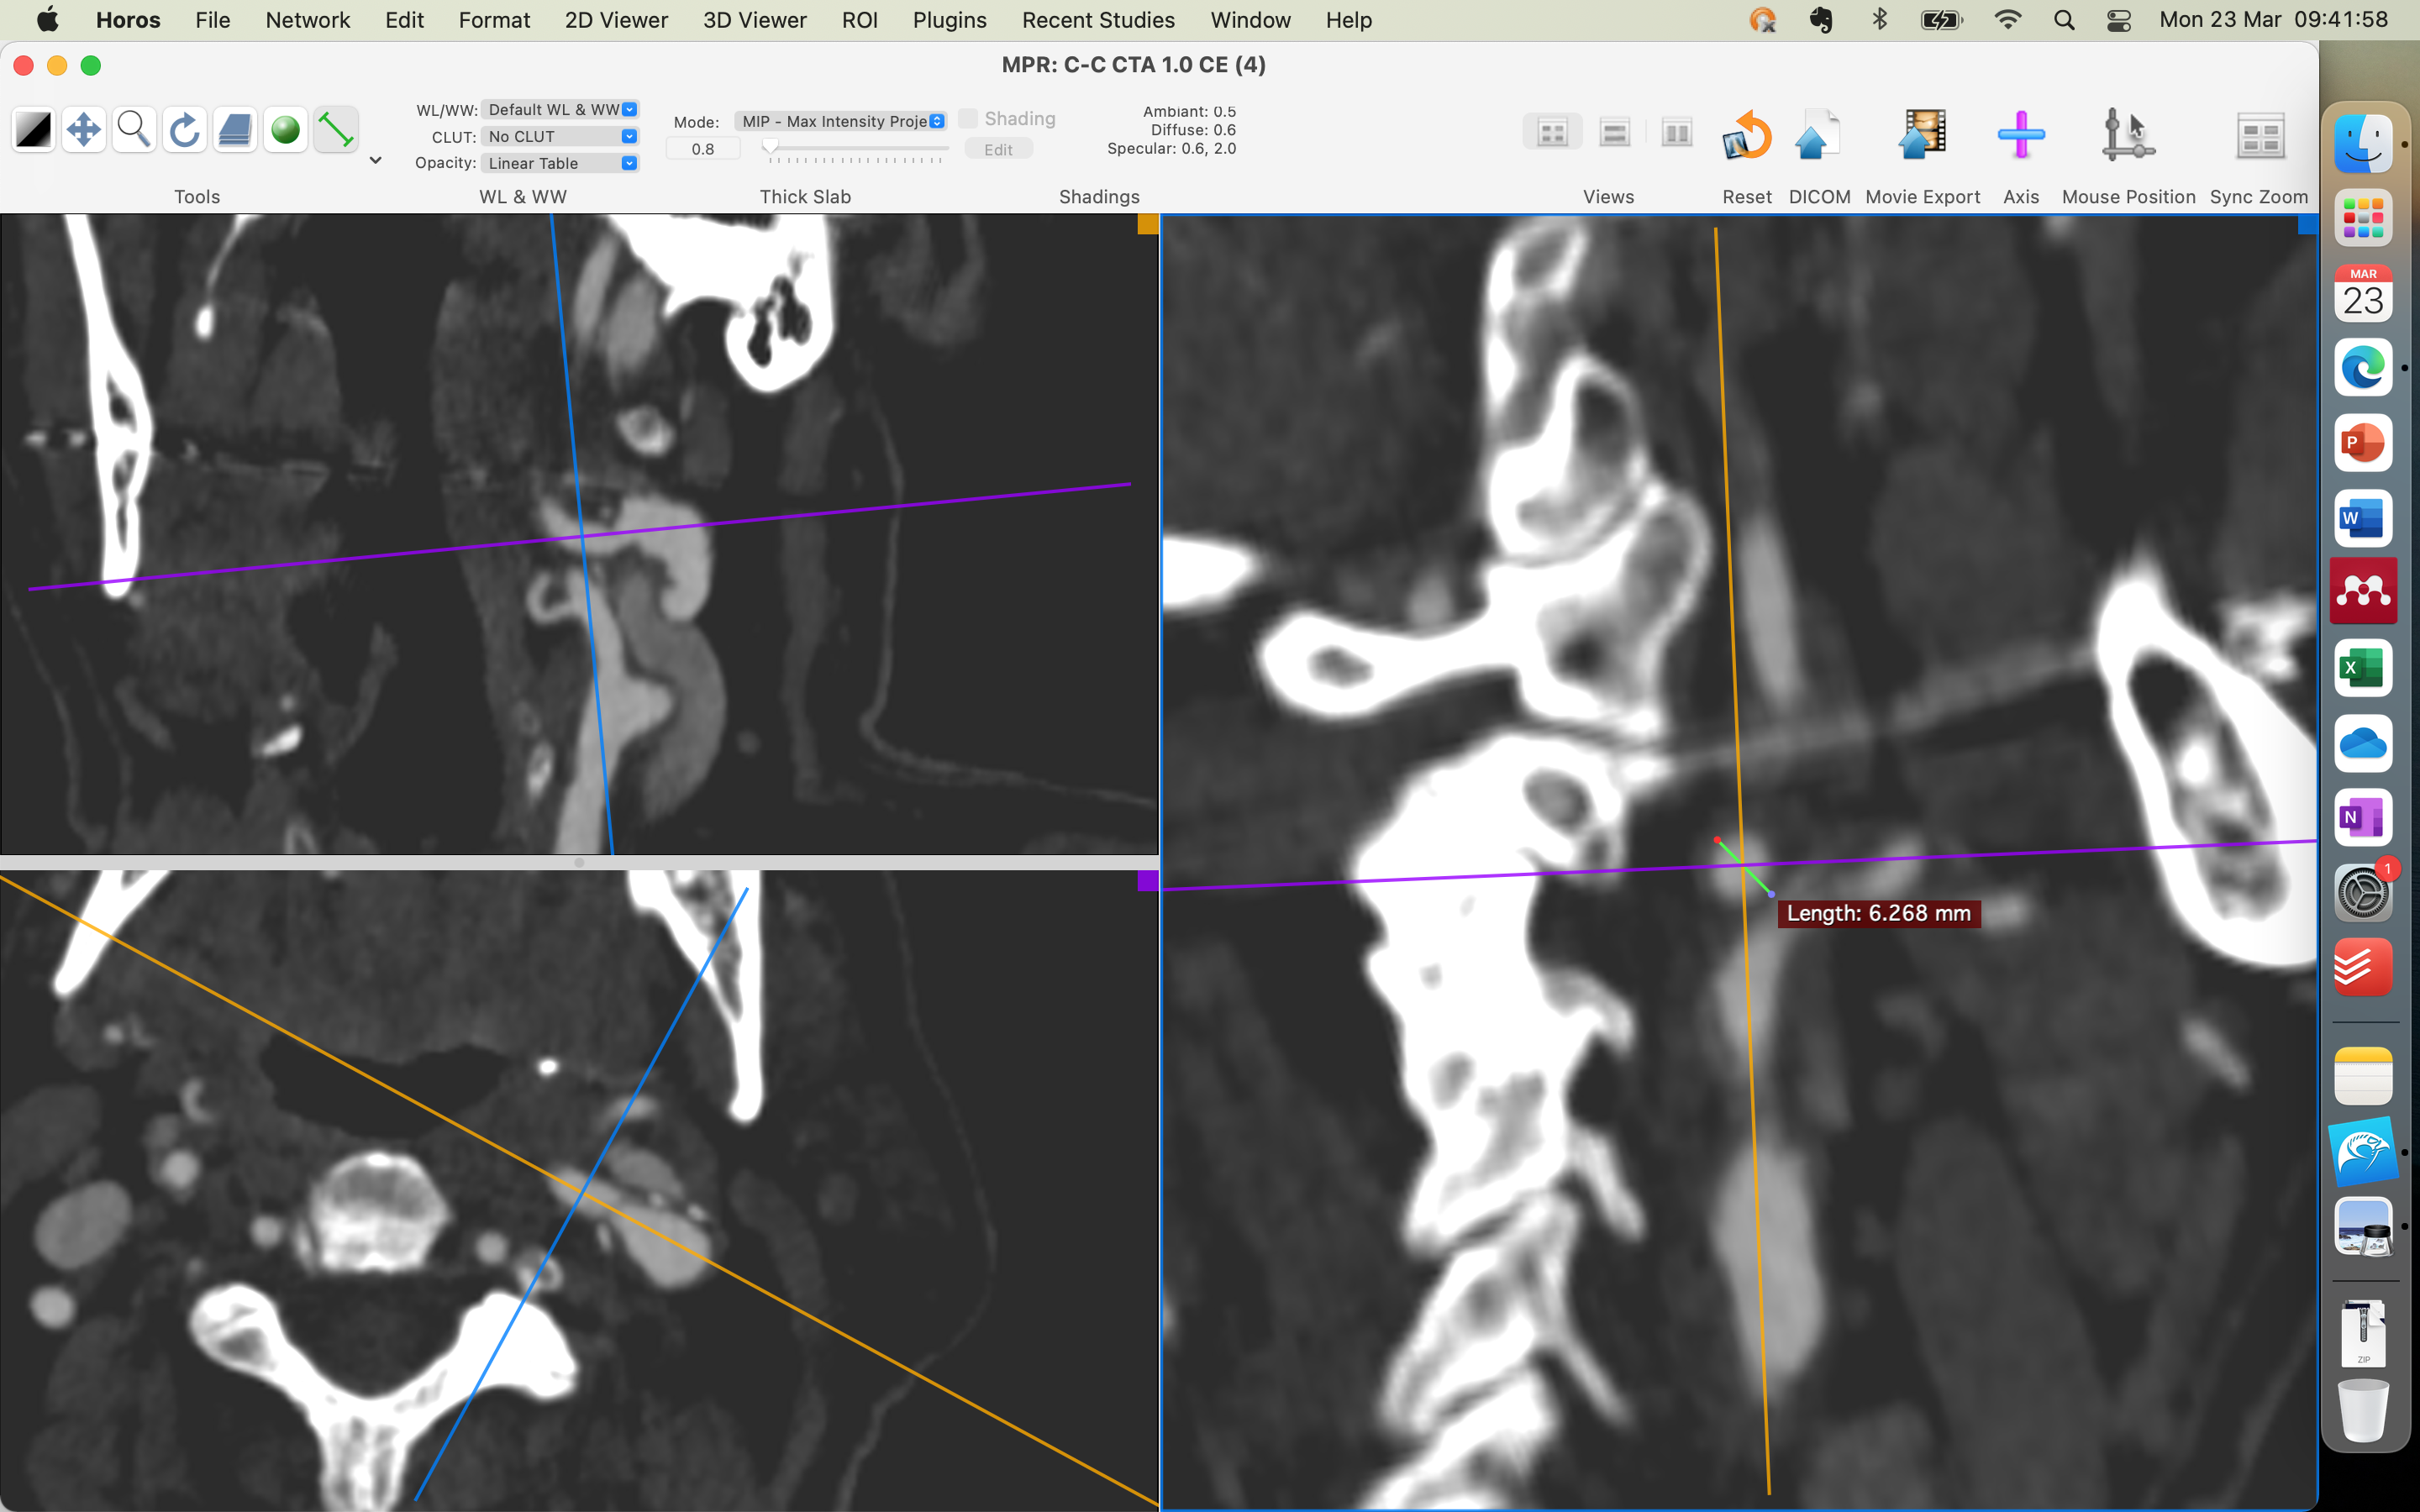

-ANGIOTOMGRAFIA ARTERIALDO CRÂNIO(04/11/2025): PLACAS ATEROMATOSAS PREDOMINANTEMENTE CALCIFICADAS NOS SEGMENTOS INTRACRANIANOS DAS ARTÉRIAS CARÓTIDAS INTERNAS, SEM PROMOVER ESTENOSE. ARTÉRIAS CEREBRAIS ANTERIORES, MÉDIAS E POSTERIORES SEM SINAL DE OCLUSÃO OU ESTENOSE. SEM EVIDÊNCIAS DE MAL FORMAÇÃO ARTERIO-VENOSA OU DILATAÇÕES ANEURISMÁTICAS. IMPRESSÃO DIAGNÓSTICA NO LAUDO: ATEROMATOSE CAROTÍDEA , SEM DETERMINAR ESTENOSES RELEVANTES.

-ANGIO TC ARTERIAL CERVICAL(04/11/2025): IMPRESÃO DX: DOENÇA ATEROMATOSA COM IRREGIULARIDADES/ULCERAÇÕES SUPERFICIAIS NO ARCO AÓRTICO E PRINCIPAIS TRONCOS ARTERIAIS SUPRA-AÓTICOS, SEM ESTENOSE; DOENÇA ATEROMATOSA MISTA NA BIFUCAÇÃO CAROTÍDEA COM IRREGULARIDADES SUPERFICIAIS : CARÓTIDA INTERNA DIREITA: ESTENOSE LEVE(INFERIOR A 50%, CARÓTIDA INTERNA ESQUERDA : ESTENOSE IMPORTANTE NA PORÇÃO PROXIMAL( ACIMA DE 70%). SEGMENTO DE ECTASISA FOCAL NO TERÇO MÉDIO DA CARÓTIDA INTERNA ESQUERDA COM SINAIS DE ACOMETIMENTO´POR DOENÇA ATEROMATOSA.

-DOPPLER DE ARTÉRIAS CAROTÍDEAS E VERTEBRAIS( 22/09/2025): EXTENSA ATEROMATOSE CAROTÍDEA , DESTACANDO AREA DE KINGING NA EMERG~ENCIA DA CARÓTIDA INTERNA ESQUERDA QUE ASSOCIADA A PLACA FIBROCALCIFICADA DETERMINAM ESTENOSE MAIOR QUE 70%.

ESTENOSE DE 90% DE ACIE ASSINTOMATICO, ATEROSCLOSE/FIBRODISPLASIA (ESTENOSE DISTAL AO OSTIO COM DILATACAO DISTAL)

ESTENOSE ACID 60% ASSINTOMATICO

- ENCAMINHO O PACIENTE PARA SANTA CASA DE MARILIA PARA REALIZAR ARTERIOGRAFIA DE CAROTIDAS E VERTEBRAIS PARA DEFINIR SE IRA OU NAO REALIZAR ANGIOPLASTIA/ ENDARECTOMIA,